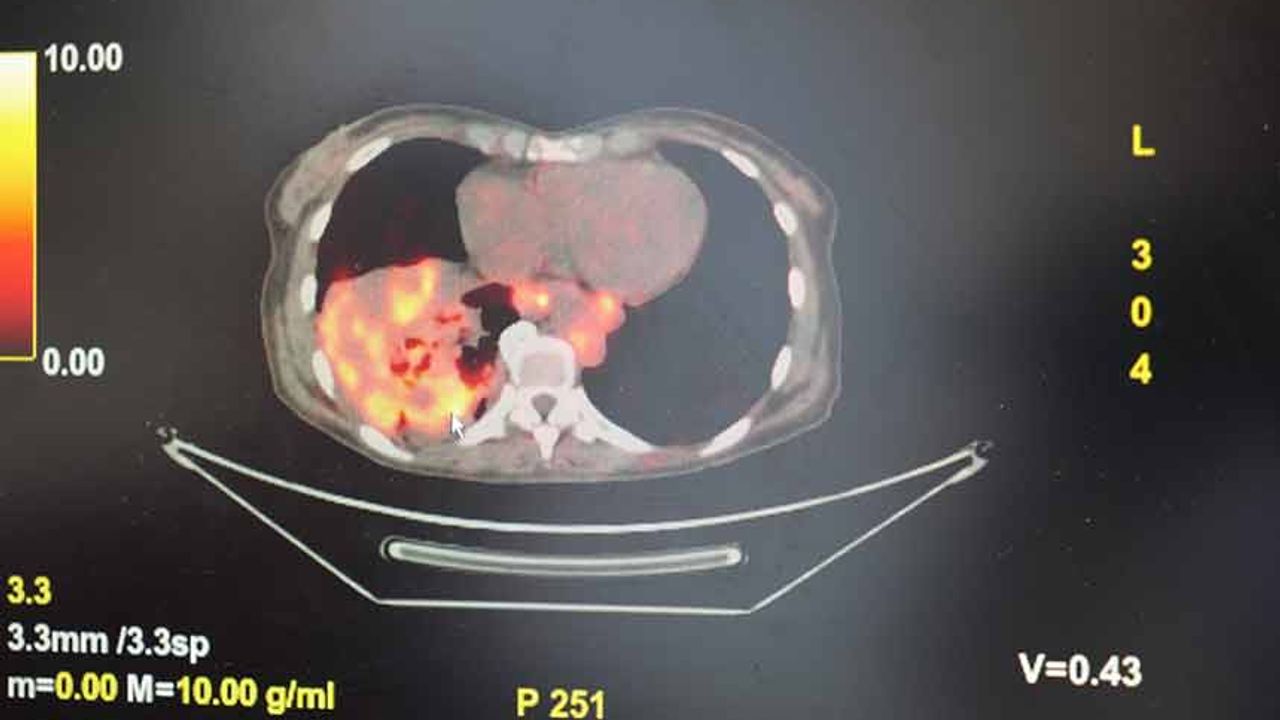

Dünyanın en prestijli tıp dergilerinden yayımlanan bir araştırma üzerinde açıklama yapan Prof. Dr. Şevket Özkaya, araştırmaya göre, sigara içmeyenlerde en sık görülen tür olan akciğer adenokarsinomu, kadınlarda akciğer kanserlerinin yaklaşık yüzde 60’ını oluşturduğunu söyledi. Prof. Dr. Özkaya, sigara dışındaki risk faktörlerinin başında radon gazının geldiğine dikkat çekerek, "Radon gazı, evlerimizde farkında olmadan soluduğumuz, renksiz, kokusuz, tatsız ve radyoaktif bir gazdır. Müsaade edilen değerlerin üzerinde solunduğunda akciğer kanseri riskini artırıyor. Radon gazı özellikle taş, toprak ve çimento gibi yapı malzemelerinde doğal olarak bulunuyor. Bu maddelerden ortama sürekli yayılan gaz, solunum yoluyla akciğerlere ulaşıyor" ifadelerini kullandı.